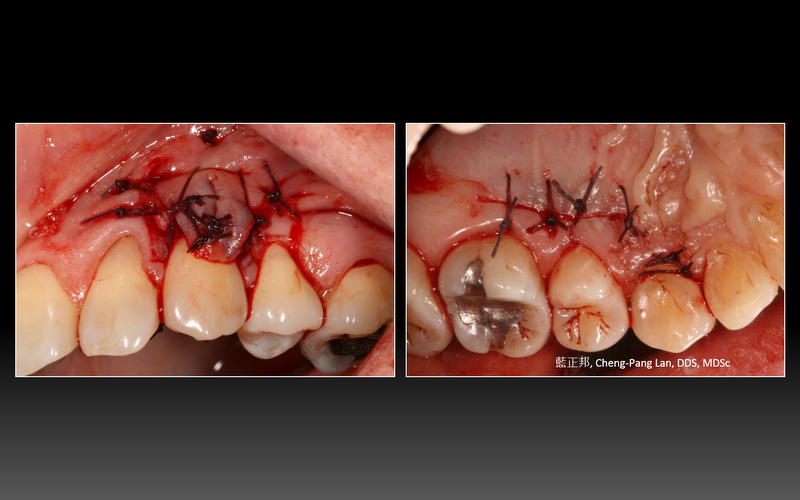

My first case of root coverage in 2008

Recipient Site: Harris’s technique, 1992

Donor Site: Bruno’s technique, 1994